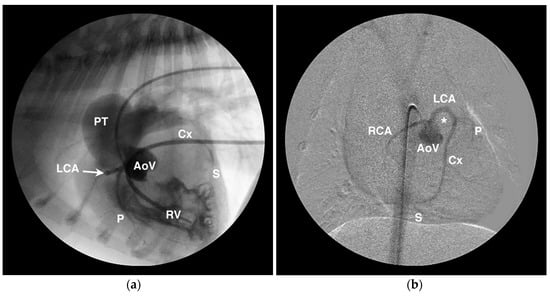

4.1. Anomalous Origin from the Aorta

4.2. Anomalous Origin from the Pulmonary Trunk

- Navalon, I.; Pradelli, D.; Bussadori, C.M. Transesophageal echocardiography to diagnose anomalous right coronary artery type r2a in dogs. J. Vet. Cardiol. 2015, 17, 262–270. [Google Scholar] [CrossRef] [PubMed]

- Visser, L.C.; Scansen, B.A.; Schober, K.E. Single left coronary ostium and an anomalous prepulmonic right coronary artery in 2 dogs with congenital pulmonary valve stenosis. J. Vet. Cardiol. 2013, 15, 161–169. [Google Scholar] [CrossRef] [PubMed]

- Laborda-Vidal, P.; Pedro, B.; Baker, M.; Gelzer, A.R.; Dukes-McEwan, J.; Maddox, T.W. Use of ECG-gated computed tomography, echocardiography and selective angiography in five dogs with pulmonic stenosis and one dog with pulmonic stenosis and aberrant coronary arteries. J. Vet. Cardiol. 2016, 18, 418–426. [Google Scholar] [CrossRef] [PubMed]